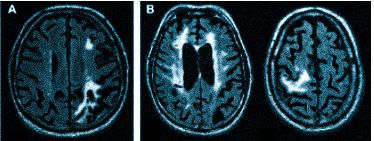

Если делать МРТ, когда не болит голова

Множественные ишемические очаги при сосудистой деменции на МРТ: отсутствие памяти на недавние события и неадекватное поведение не являются признаками старости, своевременная диагностика деменции и патогенетическая терапия помогут замедлить прогрессирование болезни

Что покажет МРТ при мигрени? Приступ мигрени выражается в расширении сосудов в мозге, после чего случается резкий (и болезненный для человека) спазм. МР-томограф фиксирует нарушения кровотока (при приступах) и отражает ишемические очаги, появляющиеся в большом количестве.